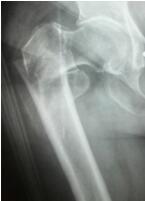

随着我国人口老龄化加重,老年髋部骨折的病人也在逐年增加。据了解,高龄髋部骨折具有并发症多、死亡率高的特点,国际上对于高龄老人髋部骨折治疗方式首选手术治疗,并且要求手术在伤后48小时内完成,越快越好。泸州市中医院通过多科协作,为髋部骨折的老年患者开启快速就医、快速检查、快速手术、快速康复的绿色通道,成...